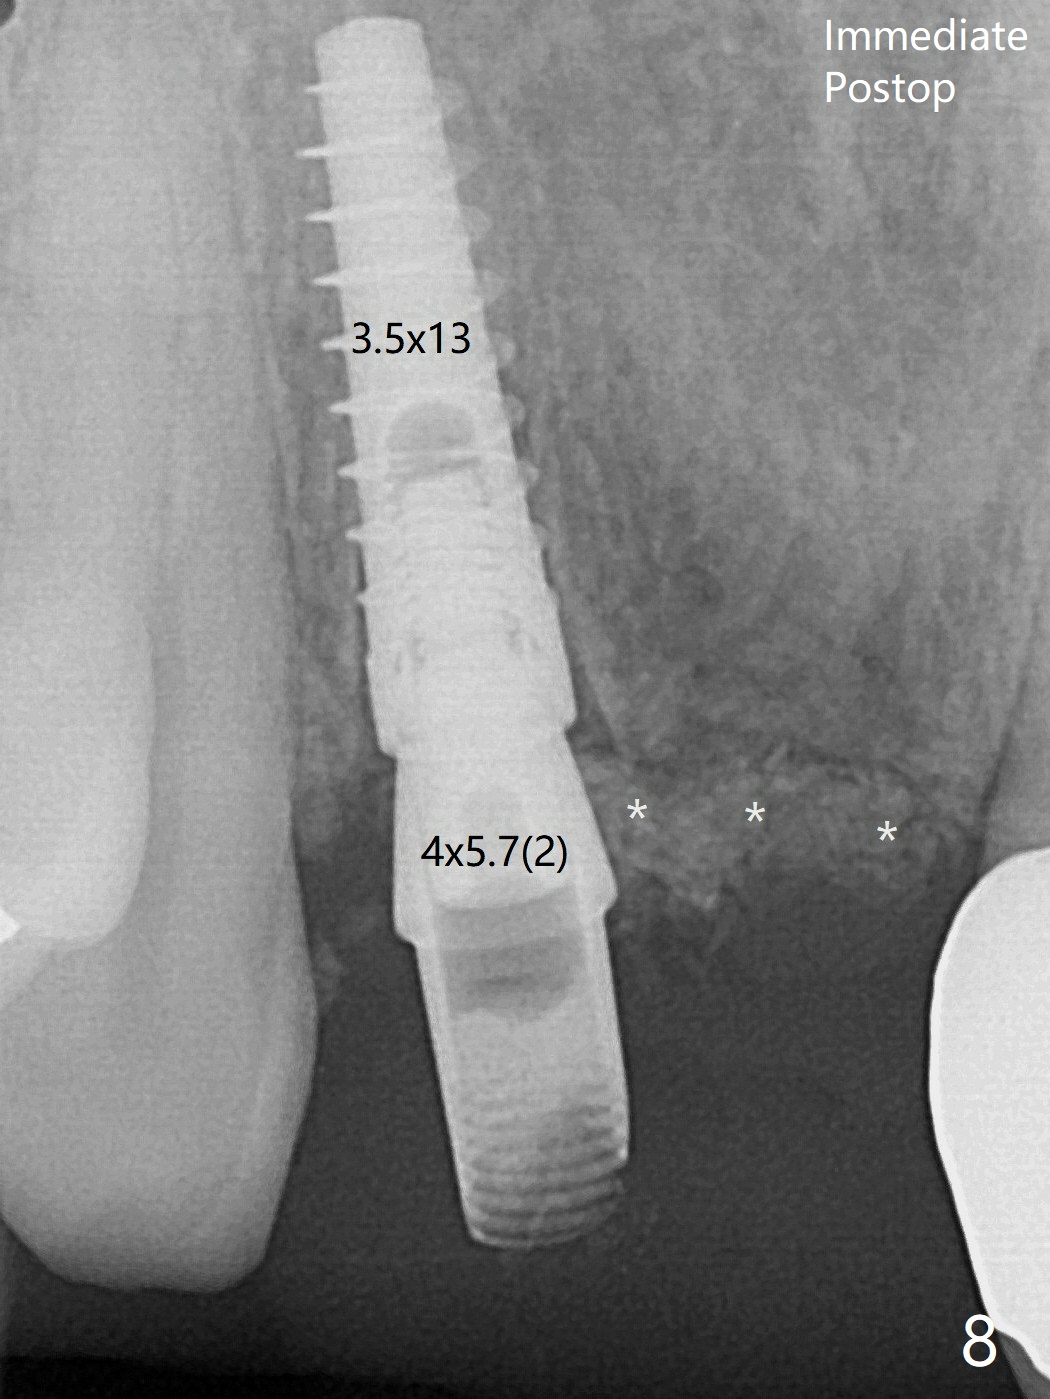

术后3.5个月植体好像整合,基台完全就位(图十六)。